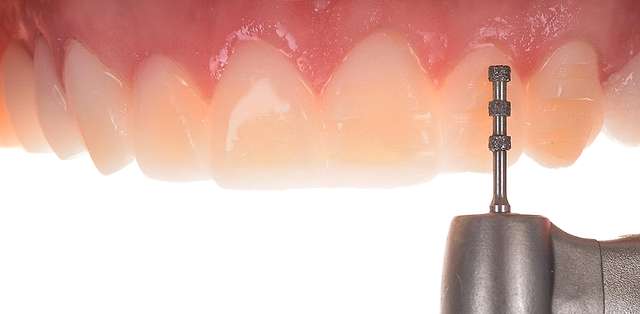

The mock-up just like a treatment plan can simulate a diverse array of procedures that vary on cases basis. In this case, we have dental implants and tissue grafts in posterior areas, on both sides, and ceramic veneers and crown lengthening in anterior side to balance the smile. As a fine detail , you can see how the dentist uses a black marker to simulate the area of the tooth which will be reduced. The mock-up, once accepted becomes a cental pillar in an interdisciplinary treatment. It will be used to determine how the gums will be remodelled , where the implants should be placed, and how the teeth need to be prepped for the future restorations.